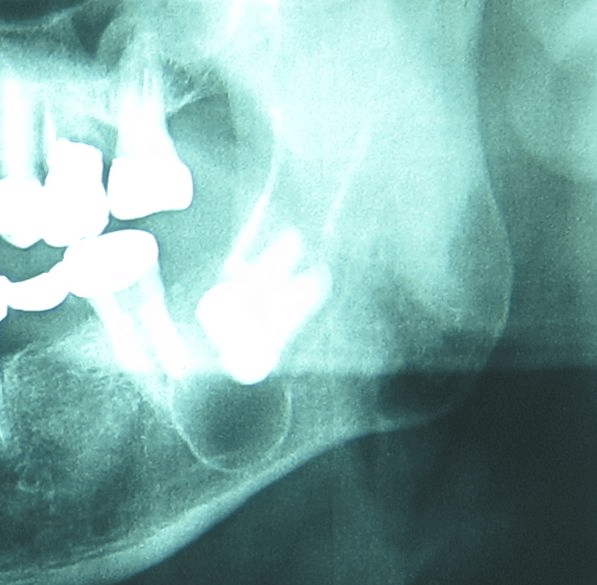

Σε πολλές περιπτώσεις παραμελημένα δόντια οδηγούν στον σχηματισμό κύστεων γύρω από τις ρίζες τους που εκτείνονται μέσα στο οστό των γνάθων.

Οι κύστεις των γνάθων μπορεί να αυξηθούν πολύ σε μέγεθος πριν δώσουν συμπτώματα όπως πόνο και πρήξιμο. Επίσης μπορεί να επεκταθούν σε σημαντικές ανατομικές δομές των γνάθων όπως το ιγμόρειο άντρο στην άνω γνάθο, τη ρινική κοιλότητα και το κάτω φατνιακό πόρο.